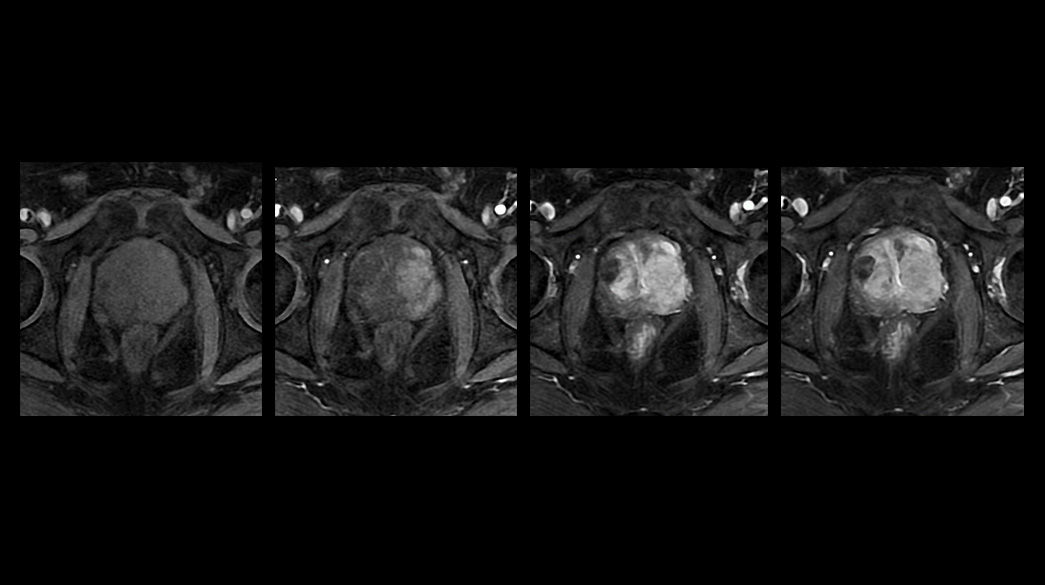

Oncology MR imaging techniques to capture anatomical and morphological data with robust tissue contrast, motion-insensitive and high temporal and spatial resolution for oncological assessment.

Oncological MRI imaging applications